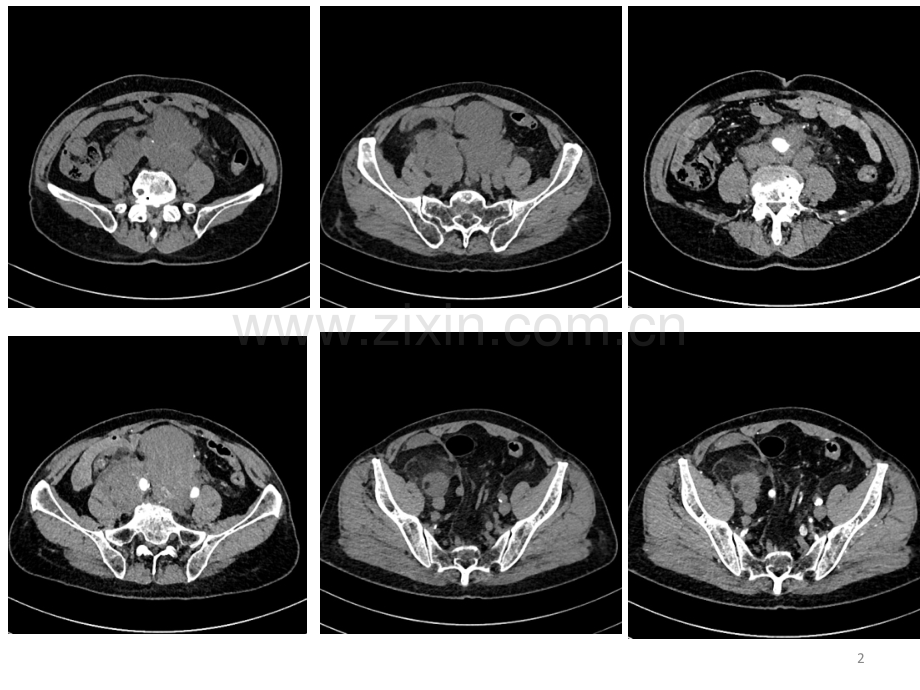

今日读片 ID号:1007263003 2017-9-21日腹部CT患者,男性,73岁,2017-6无明显诱因发现下腹部包块,局部无压痛,未引起重视。此后包块逐渐增大,并局部压痛。来我院就诊。既往有“疝气修补术”史,余无特殊病史。123病例分析思路诊断需要解决的问题l病变的部位l病变与其他器官的关系l定性诊断定位诊断是影像学要解决的主要问题4定位该病例显示很清楚,病灶位于腹膜后及盆腔内。腹膜后间隙指横膈以下和盆膈以上,腹后壁和后腹膜之间的区域,常简称为“腹膜后”。是一个疏松组织构成的大间隙,范围甚大,腹膜后间隙的疾病有损伤、感染、肿瘤、纤维化等。与周围组织关系:病变与腹膜后器官组织无明显浸润,以推压为主要表现;对周围脂肪组织主要是渗出、浸润为主要表现;对部分大血管组织被包绕生长。5定性临床情况,患者年龄肿瘤生长部位与方式肿瘤的大小、形态肿瘤的血供:动态增强肿瘤的质地、组织成分与影像学特征具特征性的影像学表现:特异征象良恶性鉴别6定性患者老年男性患者,发病时间较短。主要位于腹膜后间隙,周围脂肪间隙渗出、浸润,周围大血管被包绕,形成“包埋”征象。肿瘤体积大、范围广、形态不规则,局部呈融合性生长。肿瘤主要以软组织密度为主,盆腔右侧区肿块内可见混杂少许脂肪密度影。延迟强化,强化尚均匀,周围血管局部可见充盈缺损样改变。右侧腹股沟区肿大淋巴结。7综合判断考虑:腹膜后及盆腔内多发软组织肿块,考虑恶性肿瘤,脂肪肉瘤可能,并右侧腹股沟淋巴结转移。8病理结果:多形性脂肪肉瘤(中度侵袭性)9多形性脂肪肉瘤定义:包含数量不等的多形性脂肪母细胞的多形性高度恶性肉瘤。没有非典型脂肪瘤样肿瘤(高分化脂肪肉瘤)或其他方向分化(恶性间叶瘤)的区域流行病学:是脂肪肉瘤中最少见的亚型(分化性、黏液性、多形性、圆形细胞性和去分化脂肪肉瘤等5 个亚型),大约占所有脂肪肉瘤的5%,而占所有多形性肉瘤的20%。大部分发生在较大年龄(大于50岁),男女发病相等累及部位:多发生于四肢(下肢多于上肢),躯干和腹膜后次之,也可偶见于纵隔、睾丸旁区、头皮、腹/盆腔和眼眶。大部分发生在深部软组织内。10临床特征 与其他深部肿瘤一样,大部分患者主诉有质硬的肿大包块,许多病例最近有手术切除病史。总体来说,多形性脂肪肉瘤是一个高度侵袭性的肿瘤,转移率达30-50%,与疾病相关的死亡率达到40-50%。许多病人在短期内死亡,肺部是最常见的转移部位。相比之下,去分化脂肪肉瘤和高级别粘液纤维肉瘤的临床经过更长,深部软组织的多形性脂肪肉瘤的临床经过更具有侵袭性,这也强调有必要将多形性脂肪肉瘤划分出来。11病理特点多形性的梭形细胞、圆形细胞以及数量不等的异形的脂肪母细胞组成。影像学特点由于基本不含较成熟的脂肪成分,不含或仅含少量粘液成分,且容易发生坏死,故影像学表现为质地不均匀的软组织肿块。CT扫描呈骨骼肌密度,增强后呈中重度强化,其内坏死灶增强扫描不强化,MRI上T2WI表现为略高、等混杂信号。影像学需要与其他类型的软组织肉瘤或恶性纤维组织细胞瘤、淋巴瘤难以区分。注:圆形细胞型脂肪肉瘤,少见,由长期存在或复发性低分化黏液型脂肪瘤发展而来,恶性程度高。不含有较成熟的脂肪成分,不含或仅含少量的黏液成分,易发生坏死,故影像学表现为质地不均的软组织肿块。与多形性脂肪肉瘤在影像学难以区分,确诊需要依靠病理组织学检查。12131415多形性-黏液型脂肪肉瘤腹膜后不规则巨大软组织包块,内见斑点状、索条状脂肪密度区,局部有接近液性密度区;作甚实质及周围肠管受侵犯。16其它几种类型的脂肪肉瘤高分化型脂肪肉瘤:大部分成分成脂肪密度,肿块巨大,边界清晰,瘤内可见云絮样、条纹样边缘模糊的略高密度影集粗细不一间隔,血管不丰富,有强化分隔及不均质是其特点,CT所示的云絮状、条纹状略高密度影及分隔与脂肪母细胞、梭形细胞、胶原及纤维组织等成分有关17黏液性脂肪肉瘤影像学主要表现均匀的“囊状”肿块,介于水与软组织之间的液体密度,边界清楚,CT值平均20Hu左右肿块密度根据肿瘤细胞分化程度、黏液及纤维组织成分不同而密度各异,含黏液成分较多,密度低接近于水,病变实性成分较多者密度增高,呈稍低于肌密度或等于肌密度18去分化型脂肪肉瘤低度恶性的高分化型脂肪肉瘤中出现高度恶性的非脂肪源性肉瘤典型的CT表现为脂肪样成分中出现等于或高于肌肉密度肿块,可见出现钙化或骨化密度,增强扫描早期不均匀强化,两种成分界限分明,延迟扫描明显均匀强化19脂肪肉瘤主要由大小及范围不一的脂肪成分及非脂肪成分构成。分化良好-黏液型脂肪肉瘤,形态较为规则,可见大范围的脂肪密度或信号;分化约成熟,脂肪密度越低或信号越接近皮下脂肪信号肿块内见厚薄不一的软组织分隔及结节,尤其比较厚的分隔及大于1cm的结节,在病理上去分化、黏液变及多形性的可能性大幅度增大,增强扫描强化明显,可具有一定的侵袭性,尤其是星芒状的结节具有较高的特异性202122鉴别诊断平滑肌肉瘤占原发性腹膜后肿瘤的第2位,女性多见腹膜后类圆形或分叶状巨大肿块起源于腹膜后平滑肌、下腔静脉壁平滑肌,可侵犯血管特征:实性肿块,信号/密度欠均匀,其内可见多发不规则坏死区及囊变。不含脂肪增强实质部分不均匀明显强化,也可呈不规则环形强化钙化少见当脂肪肉瘤内不含有成熟脂肪成分时,两者很难鉴别23242526平扫为软组织密度,动脉期中度强化,静脉期持续性强化,肿瘤包绕左肾动脉,与主动脉分界不清27恶性纤维组织细胞瘤占原发性腹膜后肿瘤的第3位,好发于中年男性肿块多较大,类圆形或分叶状,边缘多较清楚易侵犯周围组织器官,浸润性生长增强除坏死与钙化部分呈中高度强化常伴有坏死及不定形钙化,可能为肿瘤基质内聚集骨软骨化生病灶所致,可作为诊断本病的线索肿瘤内常局灶性出现席纹状或车轮状结构:轨道征MRI:成分复杂,含有实质部分、囊变、出血、黏液间质及纤维组织等,MRI表现复杂。T2WI“水果盘征”为恶性纤维组织细胞瘤的特征性改变282930CT显示“轨道征”31淋巴瘤 发热、盗汗,可有腹痛 非霍奇金淋巴瘤多发生于50岁以上,霍奇金淋巴瘤多发发生在15-35岁 CT:腹膜后沿大血管分布的界限清楚的多发肿大淋巴结,伴或不伴有局部融合,形态不规则,密度均匀,出血、坏死、钙化少见。增强动脉期无强化,或轻度强化,静脉期轻度或中度持续强化,延迟期病变均匀持续性强化,少数中央坏死的表现为环形强化 T1WI稍低、T2WI稍高信号,信号均匀,增强检查轻中度均匀强化3233淋巴结转移瘤通常体积较小,表现为腹膜后多个肿大淋巴结,可以融合,中间有坏死的成环状强化,结合原发肿瘤病史容易鉴别34总结腹膜后病变的诊断步骤第一步:是否是腹膜后?第二步:是否是脏器来源的?与脏器关系第三步:寻找特殊征象第四步:血供情况?肿瘤的良恶性鉴别 单从肿瘤的大小及外观上有时候很难认其良恶性,需要结合肿块与周围的关系、淋巴结增大等综合表现约85%间叶组织肿瘤为恶性,而神经源性肿瘤以良性居多实质肿瘤:较大的实性肿瘤多为恶性,可呈不规则分叶状或多结节融合状,与周围组织界限不清或有浸润,有淋巴结增大囊性肿瘤:常为良性,其生长缓慢,均有完整的包膜,边缘清楚35 影像诊断结论非最终确诊结果,我们应尽可能准确的给出肿瘤部位、范围及与邻近组织关系,特别是与血管的关系,便于临床治疗、手术方案的确定。36谢谢各位老师,请给予批评、指正37此课件下载可自行编辑修改,供参考!感谢您的支持,我们努力做得更好!38

展开阅读全文